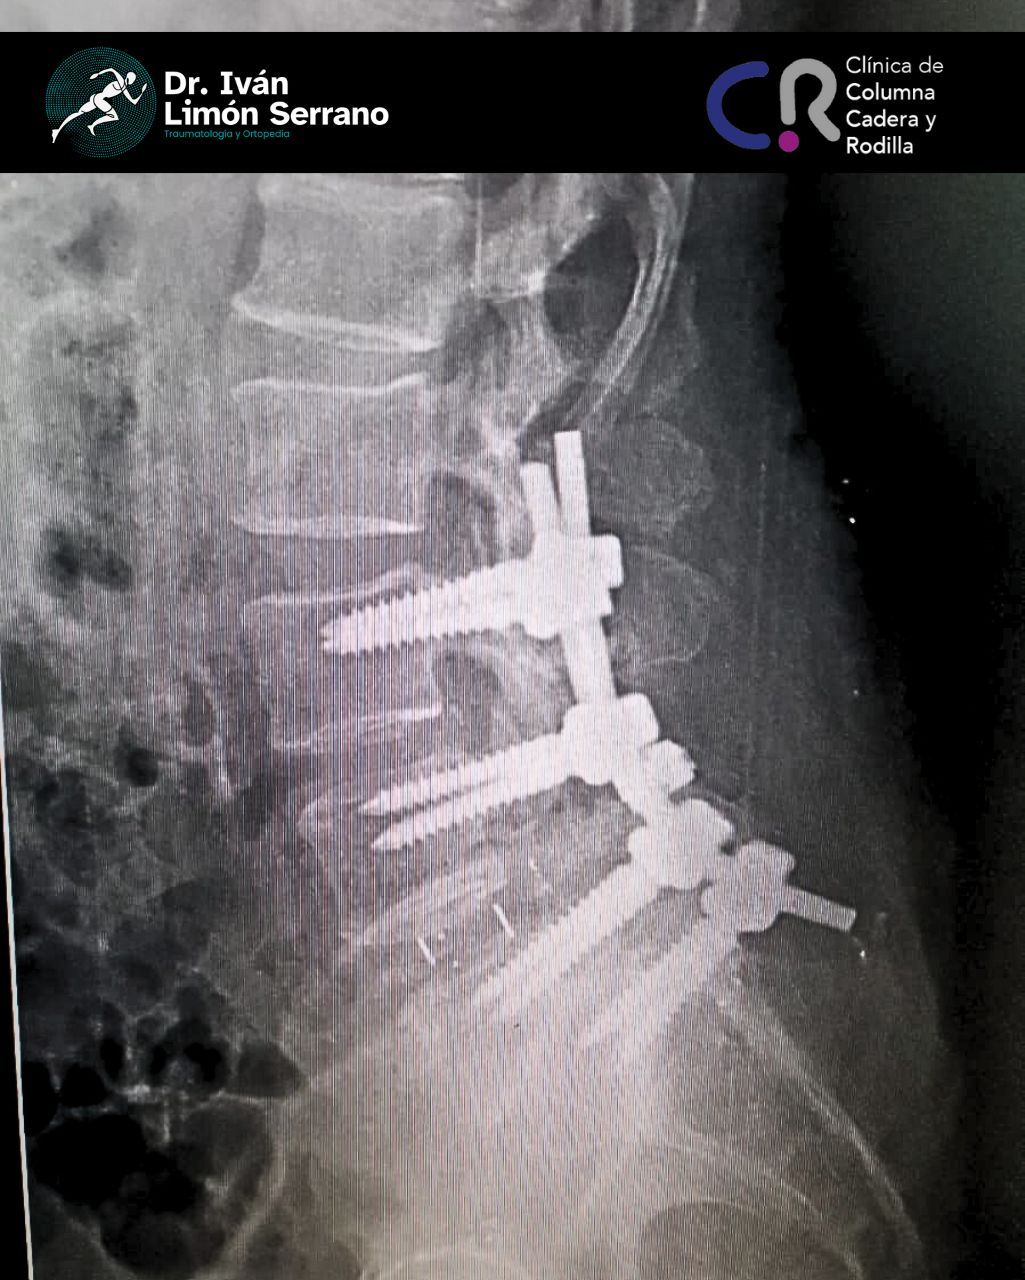

• Cirugía de columna

• Cirugía columna